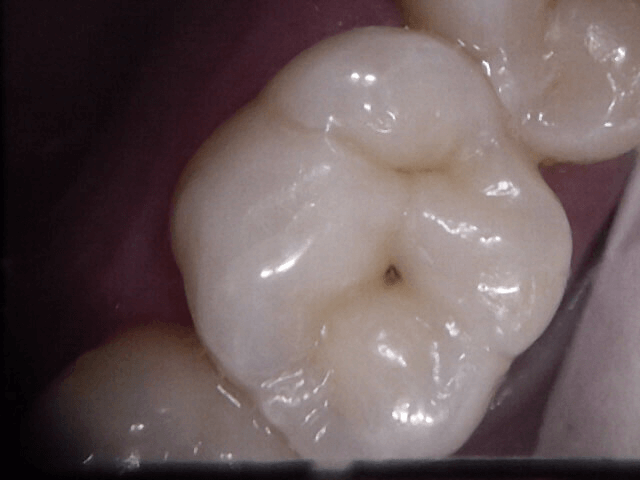

Dental Sealants and Painless Preventative Fillings in Guelph

Sometimes despite proper brushing and flossing, there can still be a chance of developing tooth decay in and around the grooves of your teeth. The tiny fissures and pits on the chewing surfaces and corner cusps of your molar and premolar teeth become susceptible to plaque and tartar build up that may be leading to tooth decay. Dental sealants can be an effective and long-lasting approach to preventing tooth decay and cavities where things appear to be susceptible.

In cases where it is clear surface decay is present in your hard-shell layers of your teeth, and brushing isn’t likely to stop the inevitable destruction of additional sound tooth structure, we can provide a quick, safe and pain-free solution. Preventative white fillings are typically placed painlessly and without the need for freezing. They very quickly restore a tooth to it’s more cleansable self.